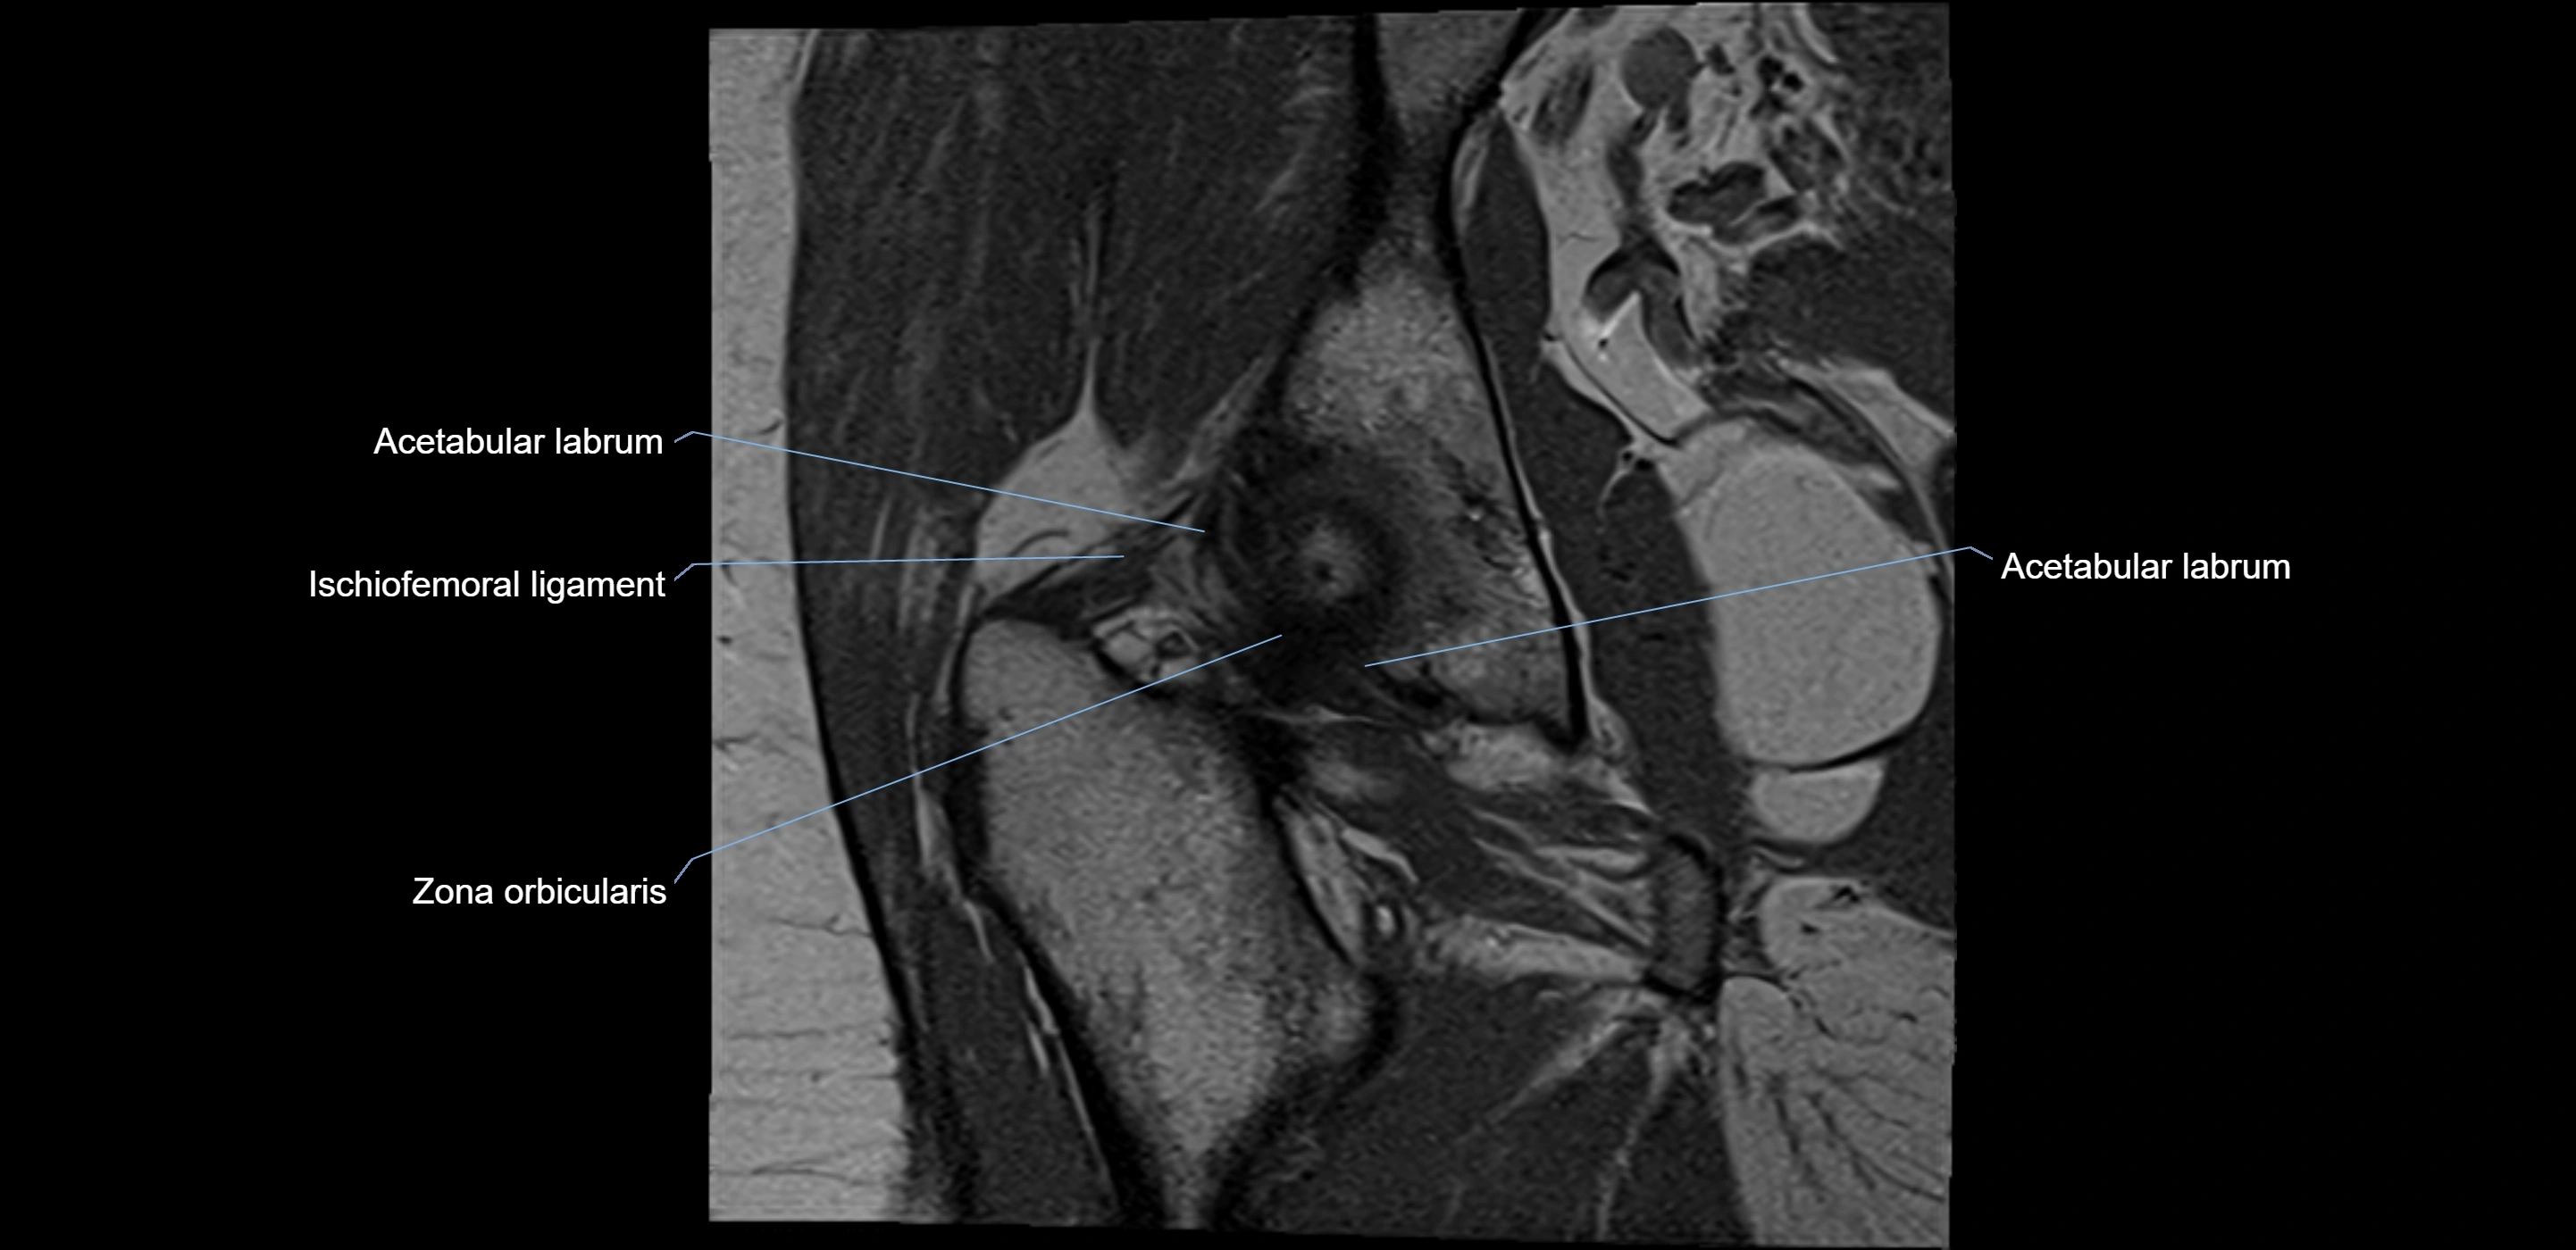

Acetabular labrum

The acetabular labrum is a fibrocartilaginous ring that surrounds the rim of the acetabulum in the hip joint. It deepens the hip socket, increases joint stability, and maintains a suction seal that preserves negative intra-articular pressure. Structurally, the labrum transitions from hyaline cartilage of the acetabulum to dense fibrocartilage at its free edge.

It is triangular in cross-section, with its base attached to the acetabular rim and its apex projecting toward the femoral head. The labrum is most robust superiorly and anteriorly, where load bearing is greatest, and relatively thinner inferiorly.

MRI Appearance

T1-weighted images:

• Labrum: low signal intensity (dark)

• Surrounded by intermediate signal joint fluid (bright on arthrogram)

• Tears: linear or focal areas of intermediate-to-high signal interrupting labral continuity

T2-weighted images:

• Joint fluid: bright, making labral tears visible as fluid extending into or around labrum

• Degeneration: may show areas of increased signal within labrum